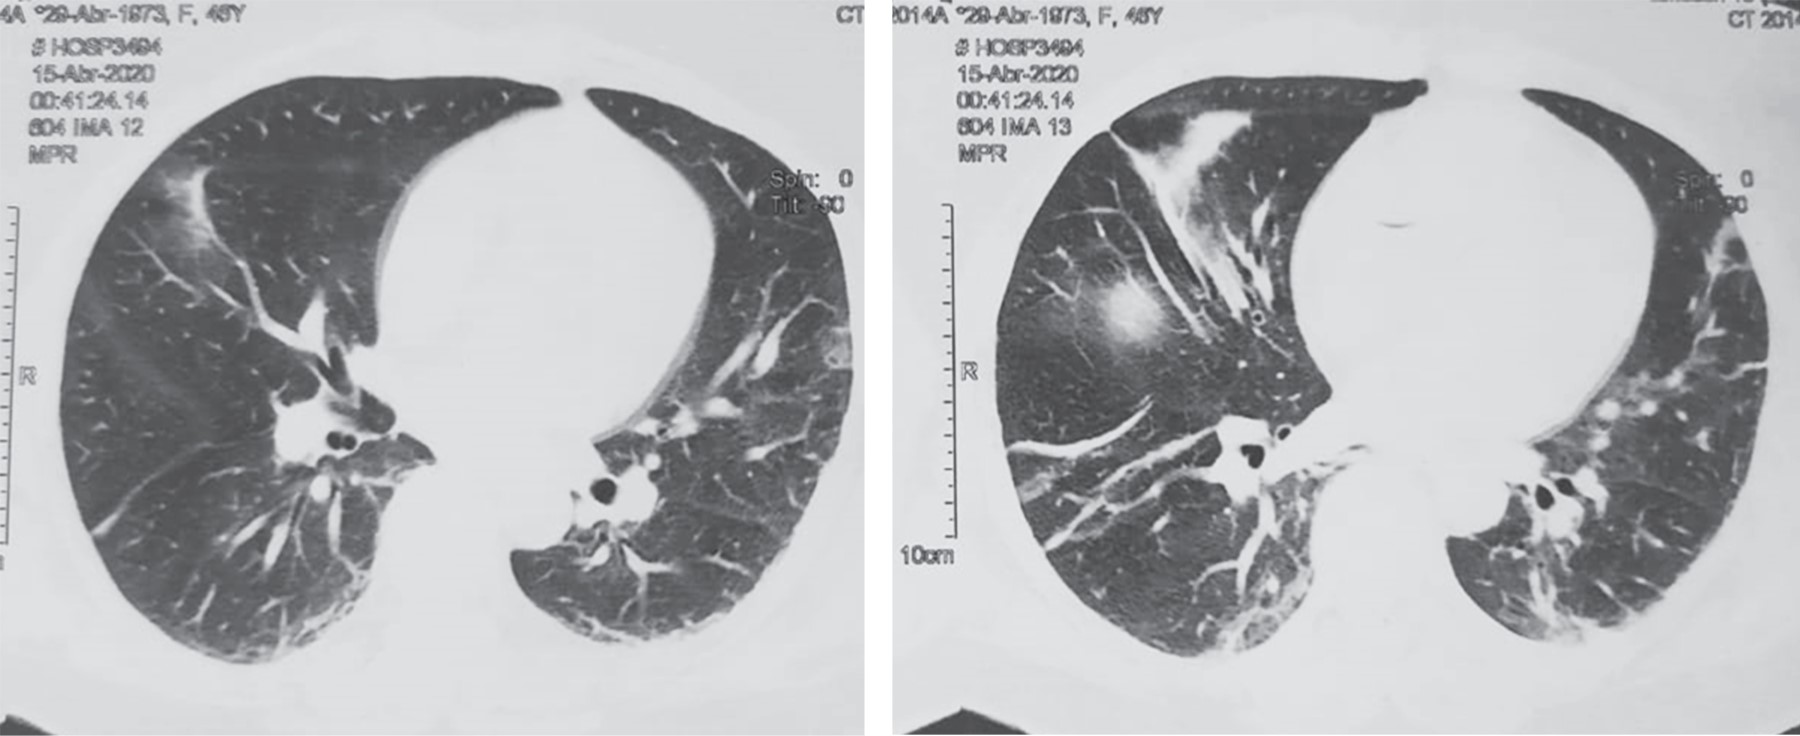

Paciente femenino de 47 años sin antecedentes no patológicos de relevancia. Tabaquismo a razón de 20 cigarros al día con índice tabáquico de 25, el cual se considera riesgo intenso para enfermedad pulmonar obstructiva crónica (EPOC); cesárea electiva hace 13 años. Inicia su padecimiento cuatro días previos a su valoración, al presentar dolor en epigastrio de intensidad 7/10 sin irradiaciones, sin desencadenantes, ni exacerbantes; acompañado de náusea y vómito en cinco ocasiones de contenido gastro-alimentario. A las 24 horas de inicio del cuadro, refiere automedicación e ingesta de butilhioscina 10 mg cada 12 horas, tras lo cual presenta leve mejoría, por lo que deja a libre evolución. A las 48 horas presenta aumento de vómitos, así como migración del dolor hacia fosa iliaca derecha, no refiere fiebre. Acude a particular a las 72 horas de inicio del cuadro, donde se administra tratamiento antibiótico con amikacina, analgésico y metoclopramida a dosis no especificadas, sin ceder el cuadro, por lo que acude a hospital particular al aumentar intensidad de dolor abdominal, en donde se le realizan estudios de laboratorio, los cuales muestran: leucocitosis de 23.3 × 10e3/μl a expensas de neutrófilos (19.48 × 10e3/μl), el resto de resultados de laboratorio sin alteraciones. Del mismo modo, al sospechar cuadro de apendicitis aguda, se solicita TC toraco-abdomino-pélvica contrastada, la cual se reporta con probable apendicitis aguda complicada con absceso localizado, así como hallazgos de broncograma aéreo y datos sugestivos de neumonía atípica por SARS-CoV-2, CO-RADS 4 (Figuras 1 y 2), por lo que deciden envío a urgencias de nuestra unidad.

Figura 1